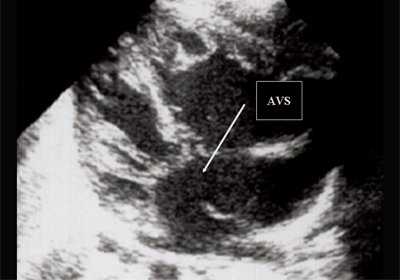

Антенатально при равных величинах давления в желудочках сердца и в предсердиях объемной перегрузки не возникает. В связи с этим ни один из эхокардиографических гемодинамических признаков, используемых у детей и взрослых, не выявляется у плода. К эхокардиографическим проявлениям порока антенатально относится только прямой признак - перерыв ультразвукового луча в области дефекта. Размеры сердца, соотношение размеров желудочков сердца не отличаются от нормы (рис. 5).

Рис. 5. Четырехкамерное сечение сердца плода. Стрелкой указан первичный дефект межпредсердной перегородки (АVS).

В равной степени это относится к дефекту межжелудочковой перегородки (рис. 6), простой форме транспозиции магистральных сосудов (рис. 7, 8), транспозиции магистральных сосудов с дефектом межжелудочковой перегородки (синдром Тауссиг - Бинга) (рис. 9), общему желудочку (рис. 10), общему артериальному стволу (рис. 10), двойному отхождению сосудов от одного из желудочков сердца (рис. 11).